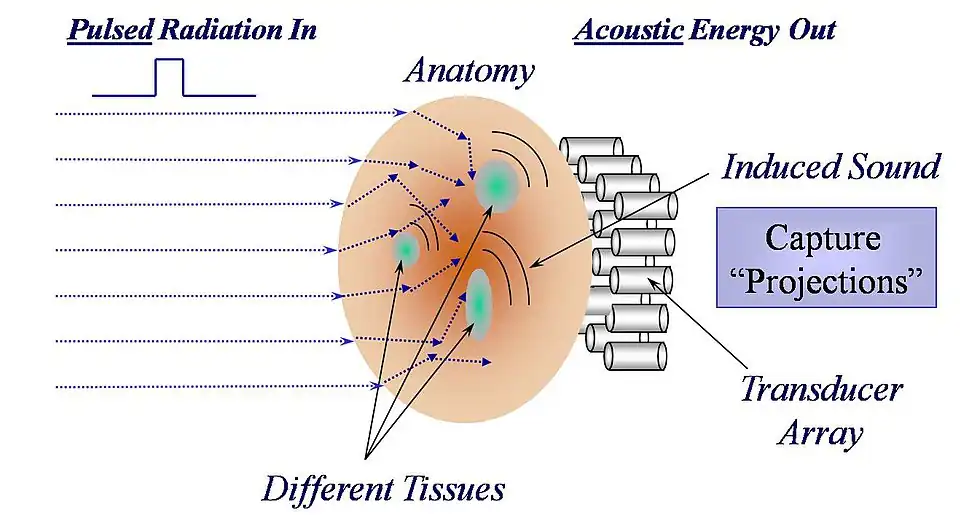

The process by which thermoacoustic waves are generated is depicted in the Figure 3. It can be understood as a four-step process:

- Biologic tissue is irradiated by an energy source that is absorbed by the body. The source of energy is non-specific, but typically consists of visible light, near infrared, radio waves or microwaves.

- The absorbed energy is converted to heat, which raises the temperature of the tissue, typically by less than 0.001 degree Celsius.

- The increase in the temperature of the tissue causes the tissue to expand in volume, however slightly.

- This mechanical expansion produces an acoustic wave that propagates outward in all directions from the site of energy absorption at the velocity of sound in biologic tissue, approximately 1.5 mm per microsecond.

Any thermoacoustic imaging device requires a source of electromagnetic radiation, be it a laser or a microwave antenna, to deliver energy to the anatomy being studied, and one or more acoustic detectors coupled acoustically to the outside surface of the anatomy, as is illustrated in Fig. 4.